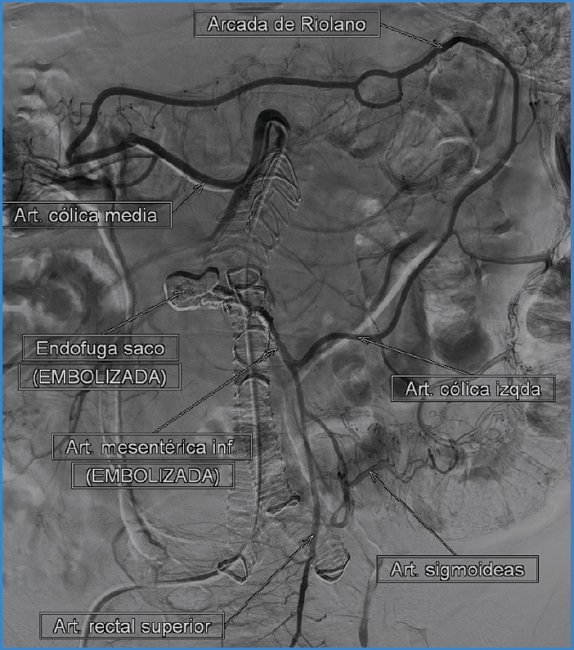

Bajo anestesia local y abordaje percutáneo femoral realizamos una arteriografía y confirmamos la presencia de endofuga, a expensas de la AMI. Posteriormente, se procede a la cateterización de la arteria mesentética superior (AMS) con catéter Cobra de 5 Fr y guía hidrofílica. Se navega por la arcada de Riolano hasta conseguir acceso a la AMI (Fig. 1). Se cambia a introductor largo de 5 Fr con punta angulada que se aboca al ostium de la AMI y avanzamos microcatéter Progreat de 2,7 Fr. Comenzamos la embolización con el despliegue de un microcoil de tipo Prestige de 6 mm × 20 cm en el ostium de la AMI con el objetivo de reducir el flujo en el interior del saco aneurismático y prevenir la migración del líquido embolizante. A continuación, progresamos el microcatéter al interior del saco aneurismático. Se intenta cateterizar selectivamente la arteria lumbar eferente de la endofuga, sin éxito. Completamos la embolización mediante la inyección de dos viales de Squid Peri (utilizando un total de 3 ml), un agente embolizante líquido compuesto de EVOH. Finalizamos el procedimiento realizando una arteriografía que muestra la correcta exclusión de la T2EL (Fig. 2).

Figura 1. Arteriografía diagnóstica en la que se visualiza la T2EL, que conecta con la AMI y una lumbar permeable.